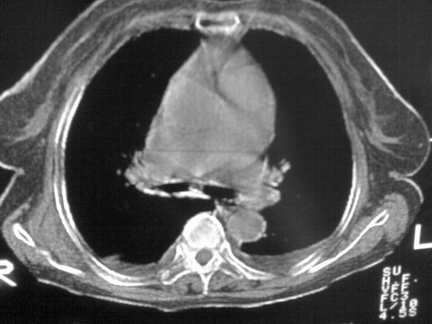

标题: CT13142:女 80 胸闷、气短、1w [打印本页]

标题: CT13142:女 80 胸闷、气短、1w

右肺炎性变,双侧甲状腺肿,胸膜肥厚。

右肺炎性变

双侧胸腔积液

缩窄性心包炎

左室为主的心脏增大。

胸膜肥厚,

右肺感染;双侧胸腔少量积液,心影增大,可能与心功不全有关;胸内甲状腺肿。

右肺炎性变,双侧甲状腺肿,胸膜肥厚,心影增大考虑心功能不全.

胸内甲状腺肿;右肺感染;双侧胸腔少量积液。

胸内甲状腺肿;右肺中叶感染;双侧胸腔少量积液;心影增大,考虑有心功能不全。